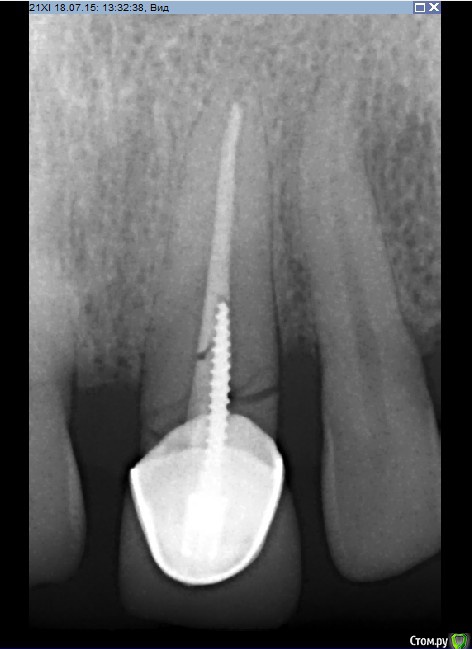

Рустам Опубликовано 20 июля, 2015 Поделиться Опубликовано 20 июля, 2015 Здравствуйте коллеги! Подскажите по клиническому случаю пожалуйста. Обратился пациент в клинику с подвижной коронкой на зубе 2.1, на рентгене диагностирован перелом корня, планируем удаление с одномоментной имплантацией и желательно с немедленной нагрузкой. Система имплантатов "Osstem", на этой системе я ранее не протезировал (работал с "Mis" и "Super Line") и вообще ранее немедленно не нагружал имплантаты. Хирург назначил удаление и иплантацию на 23.07, я смогу принять пациента только 24.07 утром, необходимо заказать временный абатмент, подскажите какой именно из каталога нужно заказать?Имплантолог заказал два имплантата Osstem TSIII SA диаметром 4,0 и 4,5.Я планирую делать временную прямым способом по ключу снятому со старой коронки во рту. Может лучше через оттиск заказать лабораторную временную?P.S. пациента эстетически все устраивало, ортодонтию не хочет. Ссылка на комментарий

Dr.Zoom Опубликовано 22 июля, 2015 Поделиться Опубликовано 22 июля, 2015 Давидян говорит, что перелом корня, впринципе, это противопоказание))) Ссылка на комментарий

Dr.Zoom Опубликовано 20 августа, 2015 Поделиться Опубликовано 20 августа, 2015 А можно по подробнее, или ссылку почитать, спасибо.если перелом корня длительное время не был диагносцирован- то существует большой риск инфецирования Ссылка на комментарий